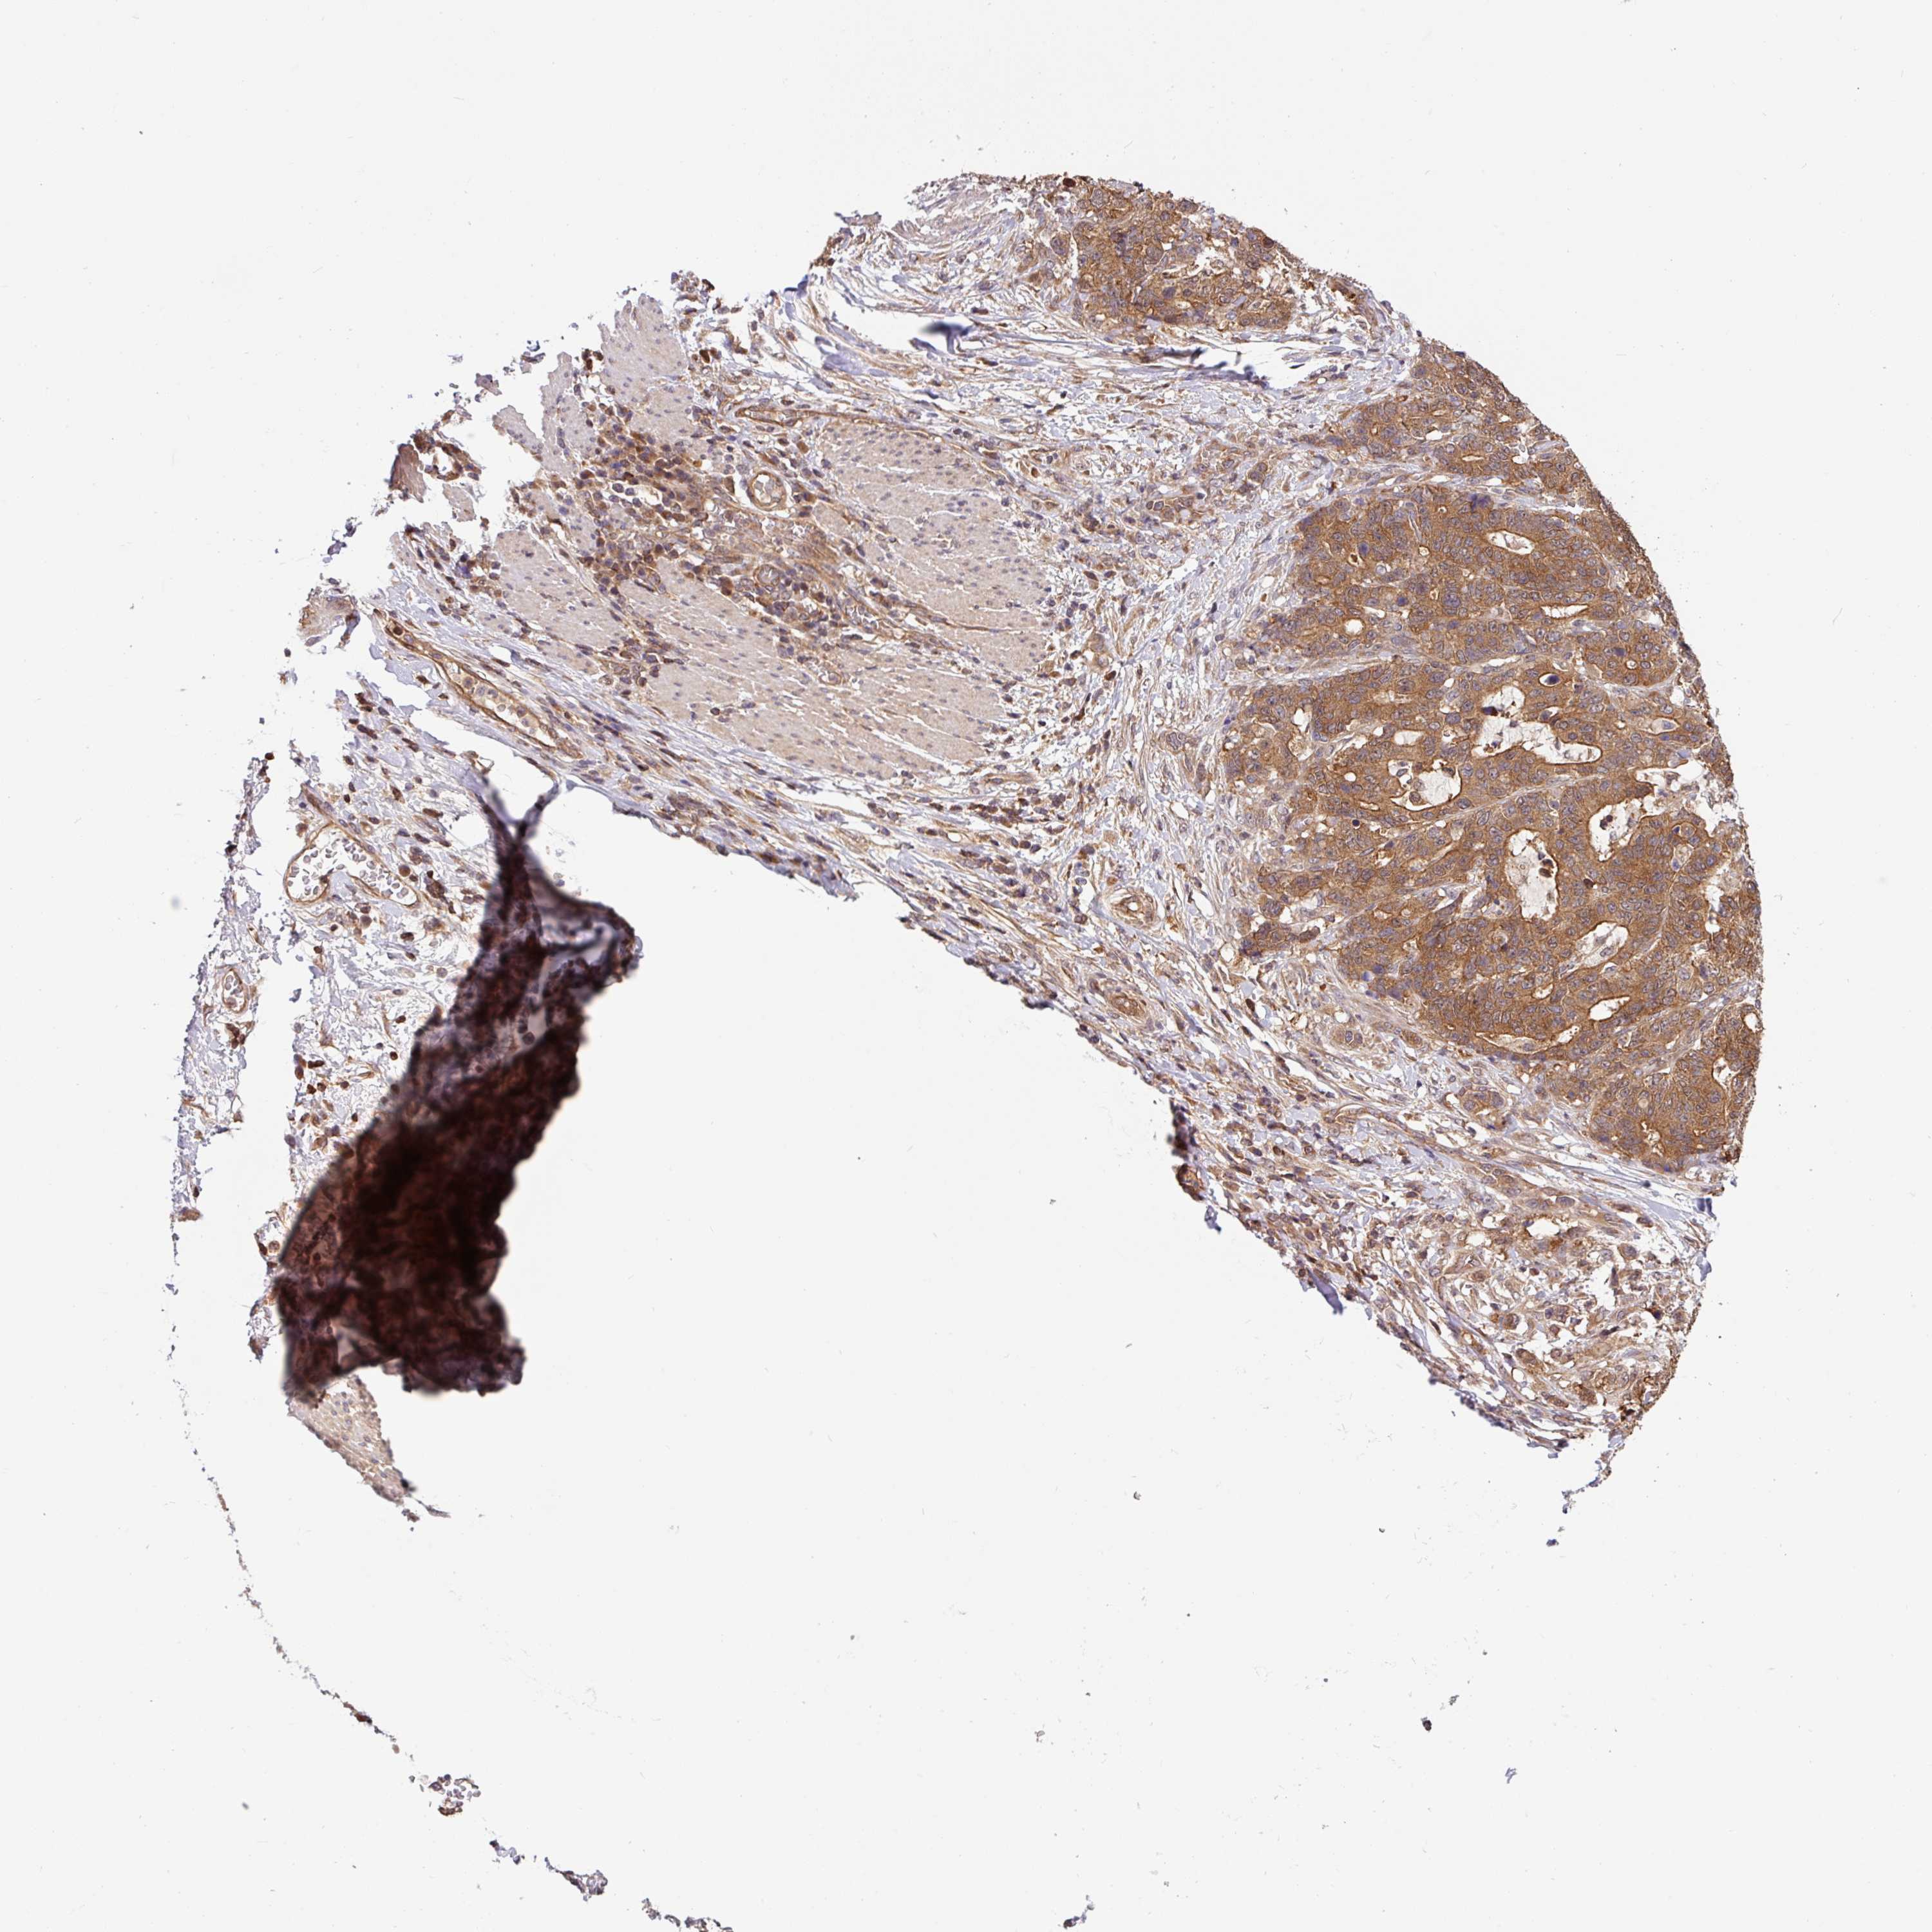

STOMACH CANCER - Protein expressioni

A mouse-over function shows sample information and annotation data. Click on an image to view it in a full screen mode. Samples can be filtered based on level of antibody staining by selecting one or several of the following categories: high, medium, low and not detected. The assay and annotation is described here.

Note that samples used for immunohistochemistry by the Human Protein Atlas do not correspond to samples in the TCGA dataset.

Antibody stainingi

Antibody staining in the annotated cell types in the current human tissue is reported as not detected, low, medium, or high, based on conventional immunohistochemistry profiling in selected tissues. This score is based on the combination of the staining intensity and fraction of stained cells.

Each image is clickable and will lead to virtual microscopy that enables deeper exploration of all samples and also displays staining intensity scores, fraction scores and subcellular localization as well as patient and tissue information for each sample.

Antibody HPA049911

Antibody CAB010161

Staining

High

Medium

Low

Not detected

Intensity

Strong

Moderate

Weak

Negative

Quantity

>75%

75%-25%

<25%

None

Location

Nuclear

Cytoplasmic/membranous

Cytoplasmic/membranous,nuclear

Adenocarcinoma, NOS